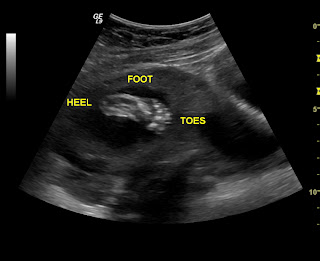

Here are some pics of our little princess!